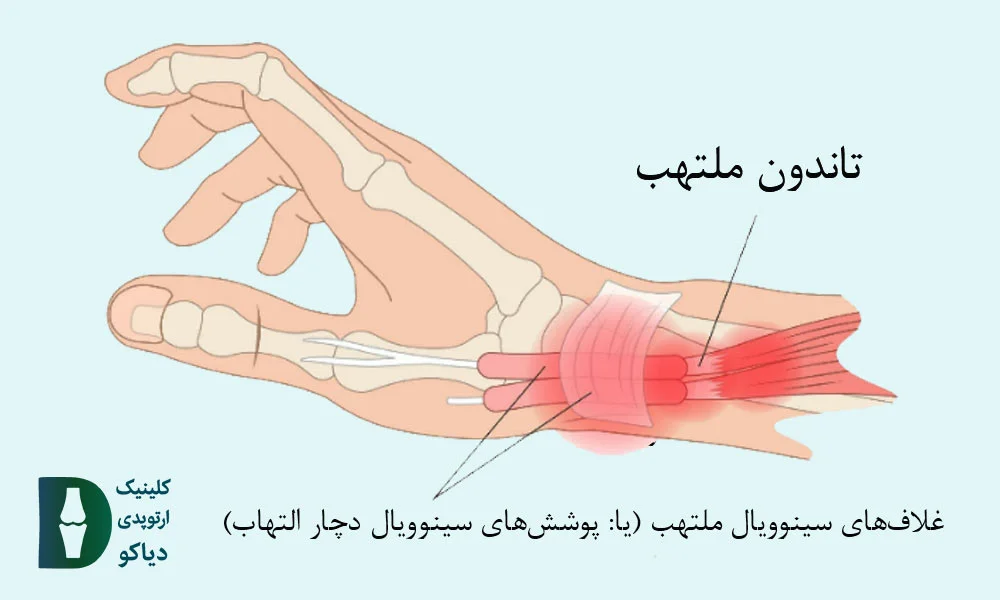

انگشت ماشهای در بزرگسالان معمولاً بهدلیل التهاب مزمن غلاف تاندون و تنگی در ناحیه رباط حلقوی A1 رخ میدهد و بیشتر انگشت حلقه یا میانی را درگیر میکند.

در بزرگسالان، انگشت ماشهای اغلب بهدلیل التهاب و ضخیمشدن غلاف تاندون خمکننده (بهویژه در ناحیهی A1 pulley ) ایجاد میشود؛ وضعیتی که باعث گیر کردن تاندون در مسیر حرکتش شده و هنگام باز یا بسته کردن انگشت، احساس قفلشدگی، صدای تق یا درد بهوجود میآورد.

در بیماران با گرید 2 و 3a، که انگشت هنگام حرکت دچار قفلشدگی میشود ولی هنوز قابلیت صافشدن دارد (چه بهصورت فعال یا با کمک دست دیگر)، درمانهای غیرجراحی میتوانند بسیار مؤثر باشند و از پیشرفت بیماری یا نیاز به جراحی جلوگیری کنند. در این مراحل، هدف درمان، کاهش التهاب غلاف تاندون، بهبود حرکت تاندون درون رباط حلقوی A1 و پیشگیری از چسبندگیهای بیشتر است.

انگشت ماشهای در کودکان (بهویژه در شست) معمولاً بهصورت مادرزادی بروز میکند و برخلاف فرم اکتسابی در بزرگسالان، دردناک نیست، اما میتواند باعث گیرکردن دائمی انگشت در حالت خمیده شود. در این حالت، کودک قادر به صافکردن شست خود نیست، حتی با کمک دست دیگر و علت اصلی این مشکل، تشکیل یک گره کوچک (ندول) در تاندون خمکننده و تنگی غلاف اطراف آن است که مانع از حرکت روان تاندون میشود.